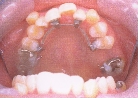

矯正歯科で撮ってくれた画像を思い切って載せました。

裏側からの装置がついている様子。

見ればわかると思うが、上の5枚が矯正前。下の5枚が矯正後。